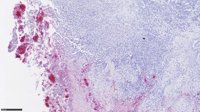

Una muestra de sangre para seleccionar el tratamiento más eficaz en pacientes con cáncer colorrectal avanzado se ha convertido en una herramienta útil para reducir la metástasis, según describe un estudio clínico pionero con participación del Instituto Catalán de Oncología (ICO).

El trabajo, publicado en la revista científica 'Annals of Oncology', se proponía abrir nuevas vías para predecir el tratamiento más eficaz en base a dos variantes genéticas que se determinan a partir de una muestra de sangre.

En el estudio clínico, diseñado por el equipo de investigadores encabezado por Martínez-Balibrea, se asignaba a los pacientes afectados de cáncer colorrectal metastásico un 'brazo control' que recibía un tratamiento estándar y un 'brazo experimental donde el tratamiento se decidía en base a dos variantes genéticas.